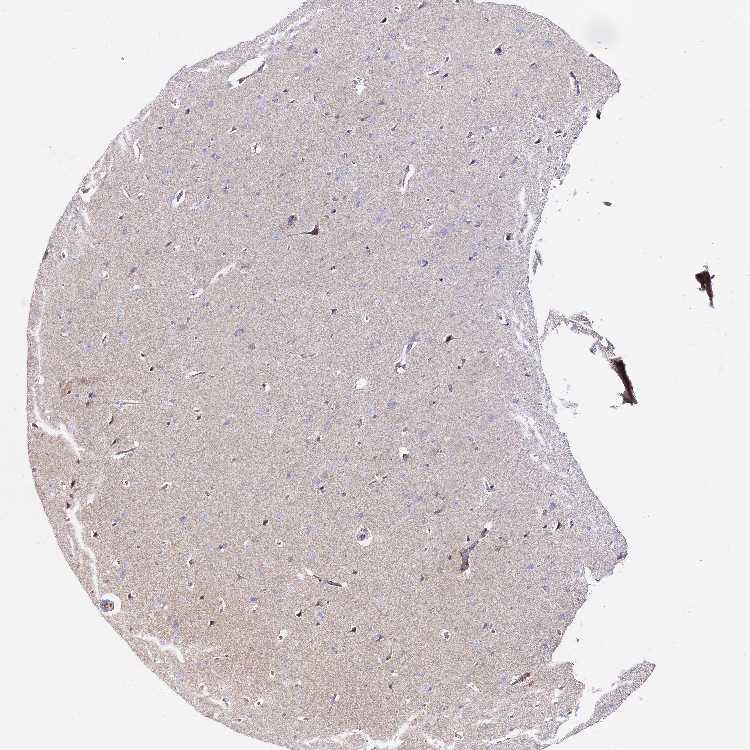

Antibody staining in the annotated cell types in the current human tissue is reported as not detected, low, medium, or high. This score is based on the staining intensity and fraction of stained cells.

Information about each individual sample is listed below, including gender, age, a tissue section image and estimated fractions of cell types. pTPM (transcripts per million) values give a quantification of the gene abundance which is comparable between different genes and samples.

Male, age 70

Cerebral cortex sample 106 pTPM: 0